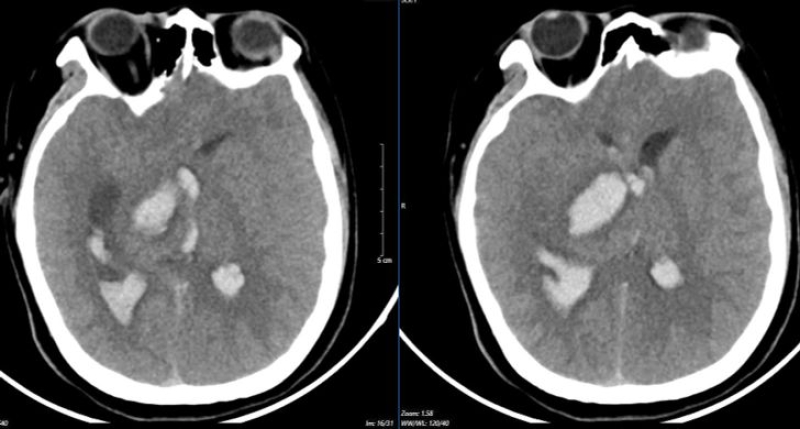

รายงานจากสื่อต่างประเทศ เด็กชายวัย 15 ปี ถูกส่งตัวเข้าห้องฉุกเฉินด้วยอาการปวดศีรษะรุนแรง จากนั้นไม่นานก็ตกอยู่ในอาการโคม่า โรงพยาบาลชั้นต้นวินิจฉัยว่า ผู้ป่วยมีภาวะเลือดออกในสมอง จึงทำการใส่ท่อช่วยหายใจ ติดเครื่องช่วยหายใจ และส่งตัวไปรักษาต่อ โดยตรวจพบว่า รูม่านตาข้างขวาขยายใหญ่ ผลการสแกนแสดงให้เห็นว่ามีเลือดออกในสมองเนื่องจากหลอดเลือดสมองโป่งพองและแตก

ดร.Le Tuấn Anh จากศูนย์โรคหลอดเลือดสมอง (โรงพยาบาลบั๊กมาย) เปิดเผยกรณีที่สองเป็นหญิงสาวอายุ 19 ปี ถูกนำตัวเข้าห้องฉุกเฉินในอาการโคม่าลึก ใช้เครื่องช่วยหายใจ และอัมพาตทั้ง 4 แขนขา ผลเอกซเรย์แสดงเลือดออกในสมองและสมองบวมกระจายเนื่องจากหลอดเลือดโป่งพองแตก